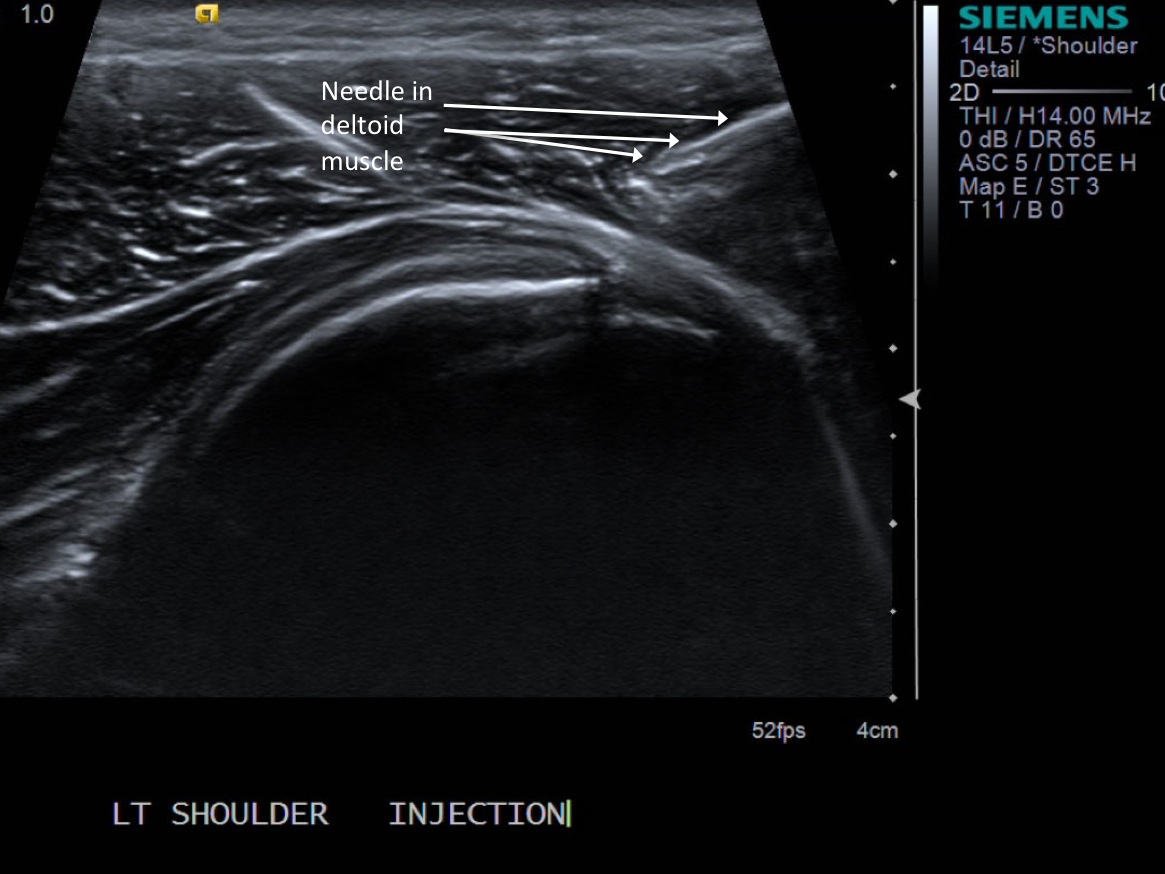

• descriptiondescription

• At this point the needle tip is not quite at the articular cartilage and still within the overlying deltoid muscle.